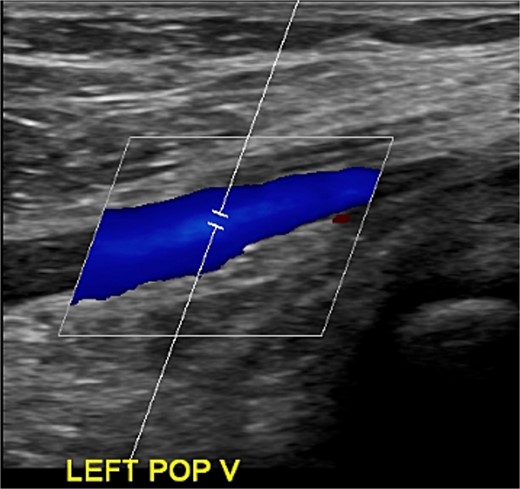

Despite initial improvement, the patient’s CRP stabilized at 5.5 μg/ml 6 days post-operatively. Consequently, a repeat I&D with antibiotic bead placement was performed on postoperative Day 7. The patient’s condition improved, with undetectable CRP levels at discharge 14 days after initial hospitalization. Four weeks post-discharge, a repeat venous ultrasound of the affect extremity was performed, demonstrating resolution of the DVT (Fig. 2). In total, the patient received 18 weeks of outpatient oral antibiotic therapy and 9 weeks of anticoagulation therapy. Six months post-hospitalization, the patient was asymptomatic and cleared to return to full activity. After 1-year post-discharge, final radiographs demonstrated no osseous abnormalities, the patient remained asymptomatic, and was released from clinic (Figs 3 and 4).

Radiography obtained 1-year postoperatively, demonstrating no acute osseous changes.